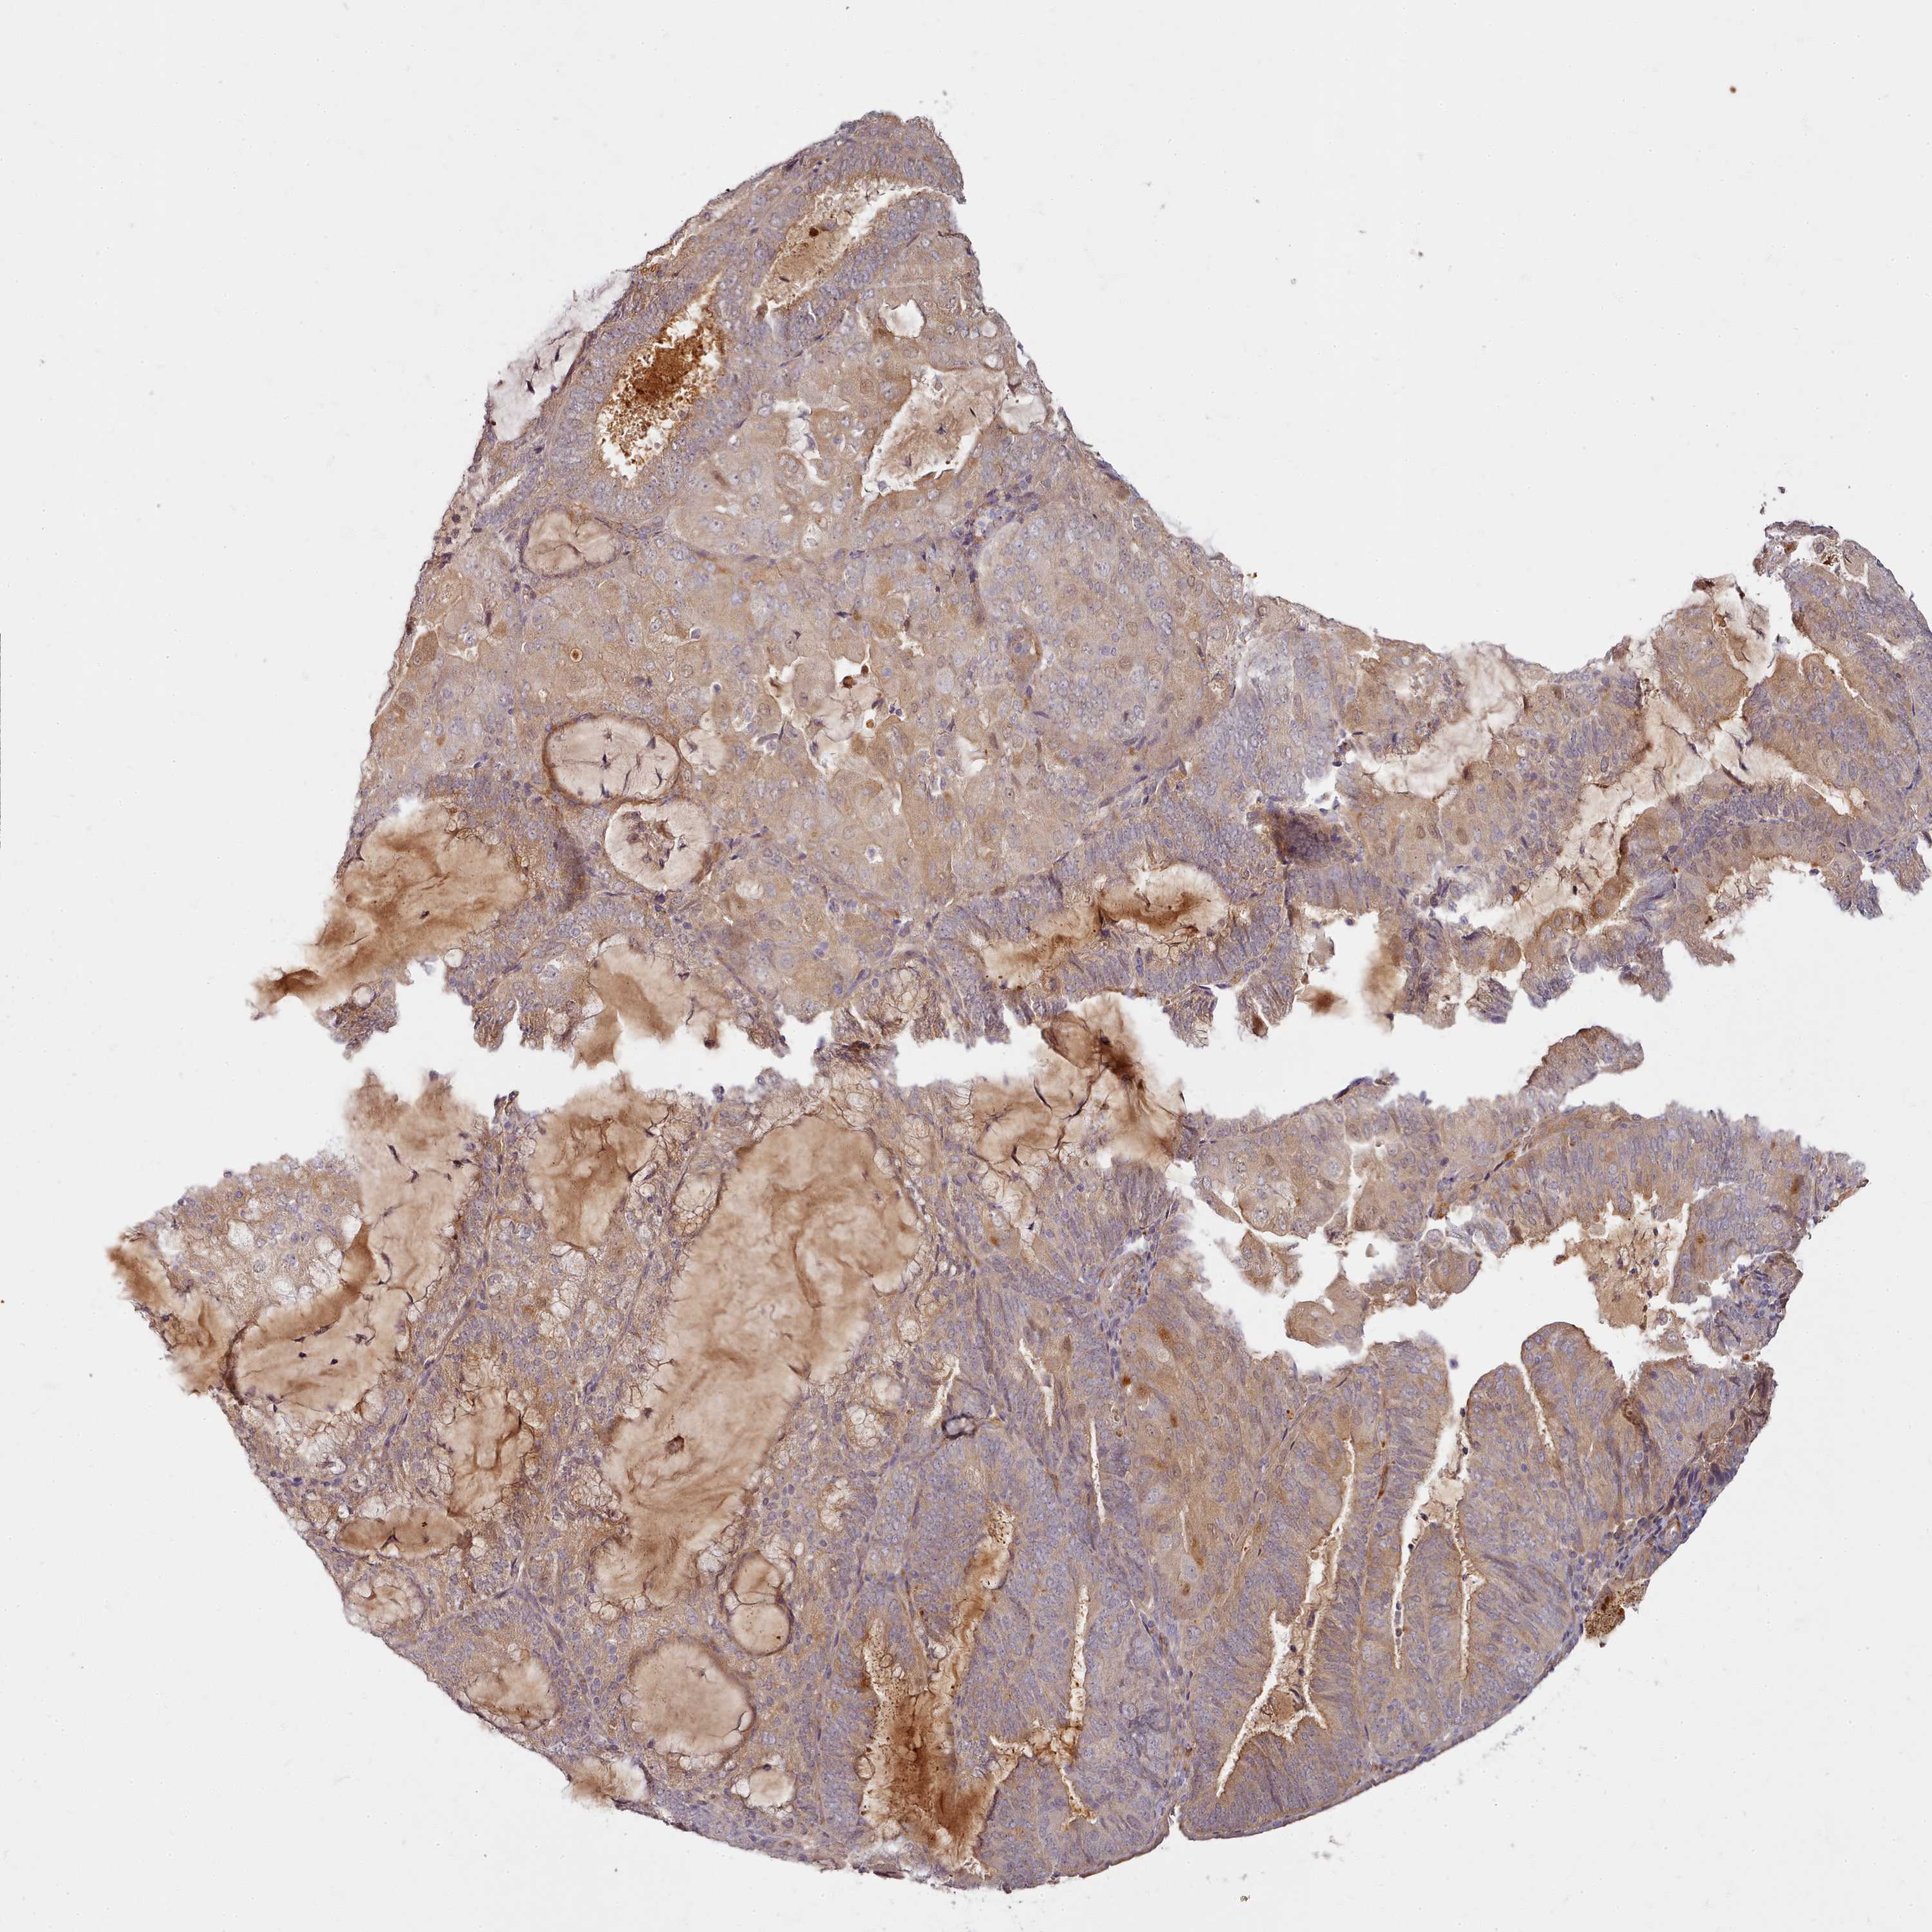

ENDOMETRIAL CANCER - Protein expressioni

A mouse-over function shows sample information and annotation data. Click on an image to view it in a full screen mode. Samples can be filtered based on level of antibody staining by selecting one or several of the following categories: high, medium, low and not detected. The assay and annotation is described here.

Note that samples used for immunohistochemistry by the Human Protein Atlas do not correspond to samples in the TCGA dataset.

Antibody stainingi

Antibody staining in the annotated cell types in the current human tissue is reported as not detected, low, medium, or high, based on conventional immunohistochemistry profiling in selected tissues. This score is based on the combination of the staining intensity and fraction of stained cells.

Each image is clickable and will lead to virtual microscopy that enables deeper exploration of all samples and also displays staining intensity scores, fraction scores and subcellular localization as well as patient and tissue information for each sample.

Antibody HPA038604

Antibody CAB025607

Staining

High

Medium

Low

Not detected

Intensity

Strong

Moderate

Weak

Negative

Quantity

>75%

75%-25%

<25%

None

Location

Nuclear

Cytoplasmic/membranous

Cytoplasmic/membranous,nuclear

Adenocarcinoma, NOS

Adenocarcinoma, metastatic, NOS